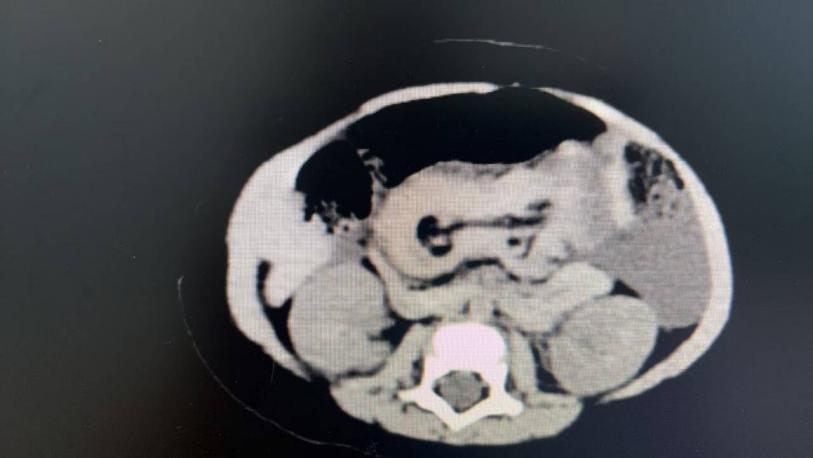

有了初步考慮,唐主任立即安排腹部彩超進(jìn)一步明確診斷,可見中上腹同心圓征(考慮回回結(jié)型腸套疊)、腸間積液。由于腸套疊程度較重、時(shí)間較長,患兒出現(xiàn)精神萎靡、尿量減少等休克表現(xiàn),懷疑存在腸壞死或腸穿孔。此時(shí)只能選擇急診手術(shù)治療,挽救患兒生命!結(jié)果術(shù)中證實(shí)了回回結(jié)型腸套疊、腸壞死的診斷,做了腸切除吻合手術(shù)。

2  患兒術(shù)前CT